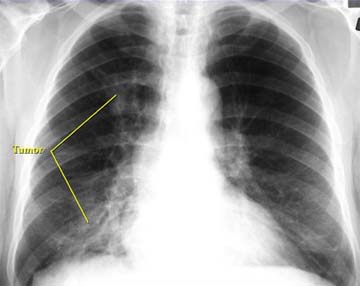

Akciğer kanseri, dünya genelinde erkeklerde önde gelen, kadınlarda ise ikinci sırada kanserden ölüm nedeni olarak gösteriliyor. Küçük hücreli dışı akciğer kanseri (KHDAK), akciğer kanserli hastaların yaklaşık yüzde 85'ini oluşturuyor. KHDAK hastalarının yaklaşık yüzde 75'i metastatik ya da ileri düzeyde bulunuyor.

İleri evre akciğer kanseri için ilaç

Küçük hücreli dışı akciğer kanseri (KHDAK) hastalarında "ALK" mutasyonu bulunanlarda tedavi şansı sağlayan ileri evre hastaların kullanabileceği yeni bir ilaç geliştirildi.